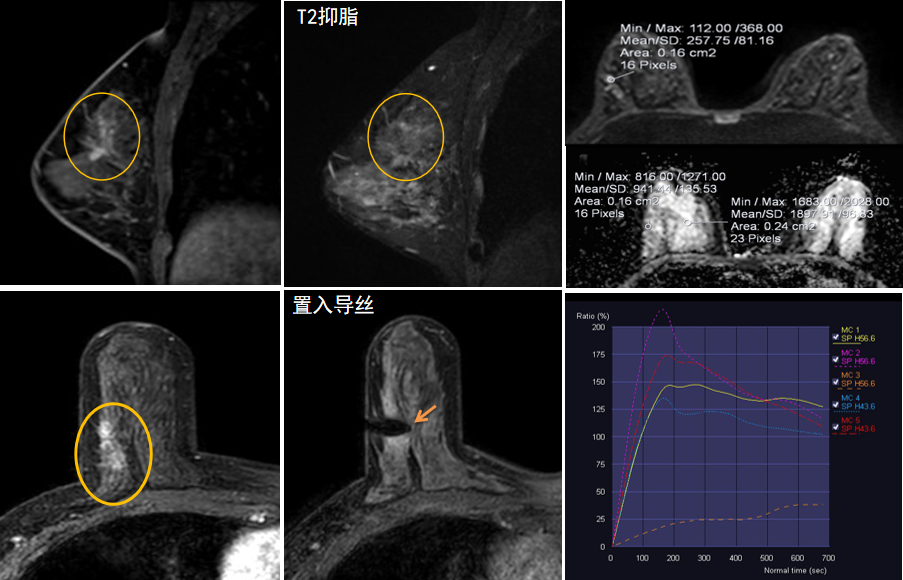

今年45歲的某女士,兩個(gè)月前行超聲檢查發(fā)現(xiàn)右乳結(jié)節(jié),乳腺X線攝影檢查提示右乳外上象限局部腺體結(jié)構(gòu)扭曲并簇狀無(wú)定形鈣化,為了進(jìn)一步評(píng)估病變性質(zhì)并確定范圍進(jìn)行了乳腺M(fèi)R平掃 DWI 增強(qiáng)的檢查,經(jīng)MR評(píng)估發(fā)現(xiàn)右乳病變范圍較廣,評(píng)估為BI-RADS 4類可疑病變,需要取得病理學(xué)結(jié)果。

陳寶瑩主任及其帶領(lǐng)的MR介入診療小組詳細(xì)詢問(wèn)了病情,分析了患者資料,并與患者和臨床醫(yī)生進(jìn)行了充分溝通,確定于手術(shù)前為患者實(shí)施MR引導(dǎo)下的病變穿刺導(dǎo)絲定位和體表范圍確定。手術(shù)前陳寶瑩主任帶領(lǐng)聶品醫(yī)師、馬小偉技師、韓愛(ài)萍護(hù)士長(zhǎng)等MR介入診療小組成員,借助MR高清的圖像顯示和定位系統(tǒng),確定病變范圍,精準(zhǔn)穿刺置入定位導(dǎo)絲,并準(zhǔn)確標(biāo)記出病變體表范圍,整個(gè)過(guò)程患者無(wú)任何不適。在定位導(dǎo)絲和體表范圍標(biāo)記的輔助下,甲乳外科劉曉敏主任精準(zhǔn)切除了病變,解除了患者的后顧之憂。

國(guó)內(nèi)外指南均建議40歲以上的女性每年行一次雙乳X線攝影(鉬靶)檢查,以篩查乳腺癌。對(duì)于乳腺癌高危人群40歲以前即建議開始乳腺癌篩查,除了進(jìn)行乳腺X線攝影(鉬靶)篩查外需要補(bǔ)充MR檢查,MR檢查敏感性最高,能夠發(fā)現(xiàn)大量X線攝影和超聲檢查陰性的可疑病變,基于多模態(tài)、多參數(shù)的結(jié)構(gòu)和功能成像的基礎(chǔ)上,MR能夠精準(zhǔn)顯示病變位置、范圍以及病變內(nèi)的活性區(qū)域,MR引導(dǎo)下的介入診療不但解決了僅在MR顯示的病變的處置難題,而且能夠精準(zhǔn)定位活性區(qū)域,保證了定位、活檢及旋切的準(zhǔn)確性。